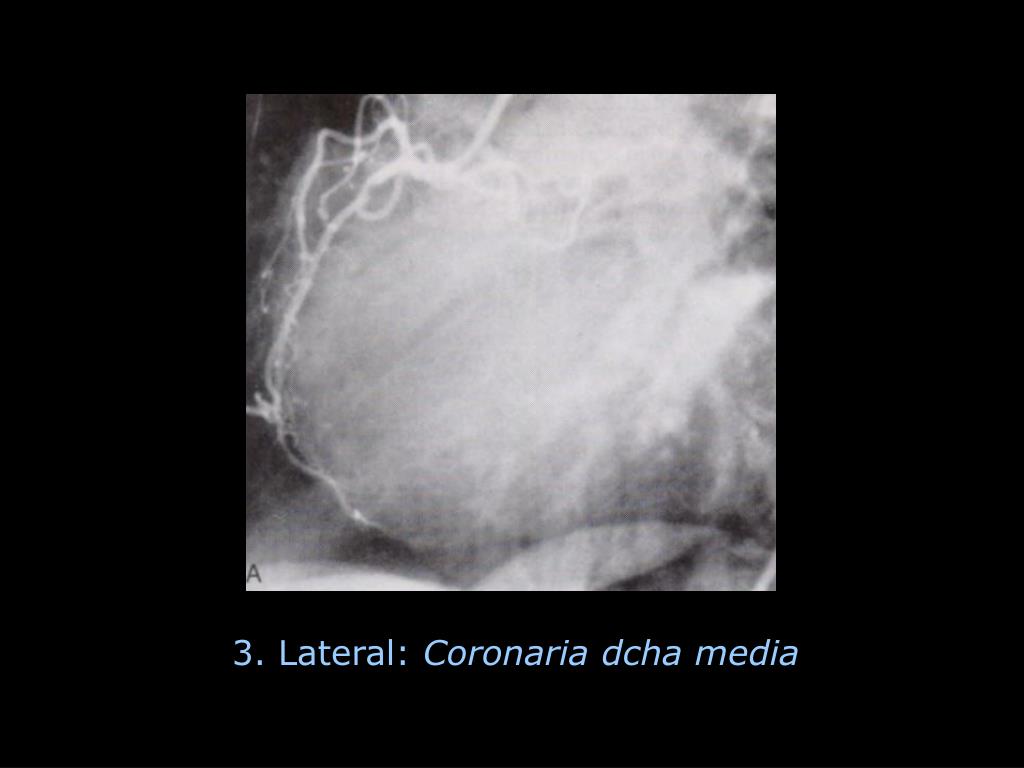

12. DOMINANCIA IZQUIERDA Descendente post. Póstero-lateral izda Arteria del nodo AV Cx DOMINANCIA BALANCEADA Descendente posterior CD Póstero-lateral izda Cx

25. 3. Lateral: Coronaria dcha media